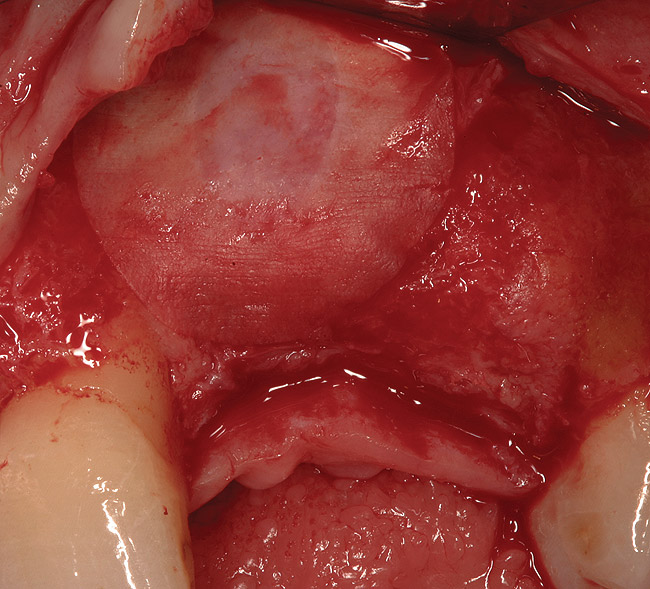

Figure 15  (Case 2) Defect after implant removal.

Figure 15